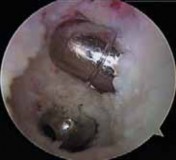

29. This process is then repeated for the PM graft (

TECH FIG 8

).

1. It is helpful to keep tension on the AL graft suture ends when passing the PM graft to ensure that the AL graft does not get pulled into the joint.

4. The arthroscope is inserted to confirm adequate position, tension, and fixation of the grafts.

--- TECH FIG 8 • The double-bundle reconstruction with the grafts in place. ### TECHNIQUES